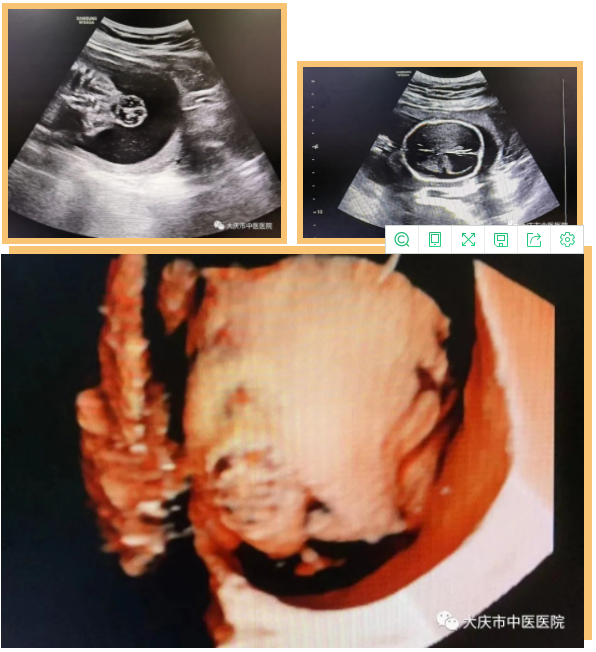

近日,超声医学科通过四维彩超筛查,为一位准妈妈做出了及时准确的胎儿发育健康提示。该孕妇为第一次妊娠,孕22周,既往超声检查结果未报异常,无创DNA结果低风险。在超声医学科进行胎儿系统筛查时,当日值班医生、超声医学科副主任王双艳,第一眼便发现胎儿头部形态异常并伴有侧脑室明显扩张,提示胎儿脑积水,考虑胎儿存在神经管畸形。经过一番认真细致的检查,发现胎儿除脑积水外,还有开放性脊柱裂、双足内翻,出现足内翻提示胎儿神经系统已经受损害。

(四维成像,结构异常更清晰)

大庆市中医医院四维彩超设备,为三星WS80A彩超诊断系统,具有极高的清晰度和分辨率。能360°全方位立体呈现胎儿表面畸形、内脏畸形和头面部畸形及宫内发育情况,如胎儿孕周、体重大小,预产期的估测,胎心率的快慢,脐带血流及脑缺氧的评估等,是应用于胎儿产前筛查、及完整记录胎儿宫内高清动态的先进超声设备。